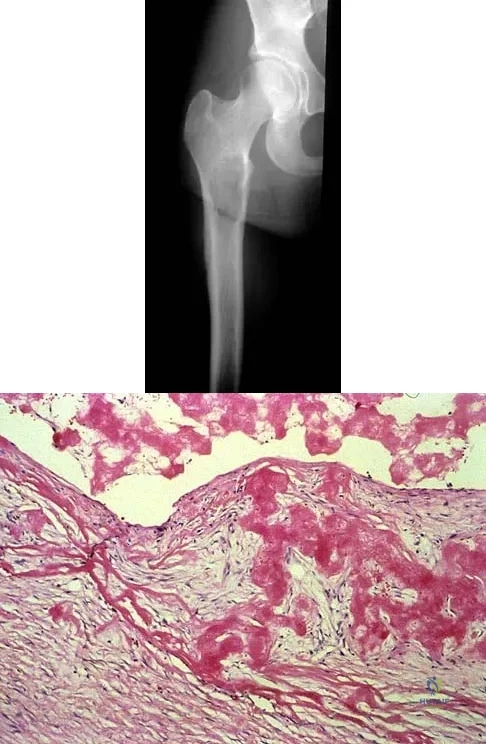

A 38-year-old woman with metastatic thyroid carcinoma has had increasing pain in the left hip for the past 3 months. An AP radiograph and coronal T1-weighted MRI scan are shown in Figures 28a and 28b. Management should consist of

Correct Answer: cemented bipolar hemiarthroplasty.

The radiograph and MRI scan reveal a lytic lesion in the left femoral neck region that extends to the lesser trochanter. Although external beam radiation and radioactive iodine infusion may be helpful in controlling the local disease, the patient is at high risk for femoral neck fracture given the location of the lesion. Prophylactic surgery is indicated; therefore, the treatment of choice is a cemented bipolar hemiarthroplasty. The use of a compression hip screw and side plate or an intramedullary nail has a high likelihood of failure with disease progression. Postoperative treatment with radiation therapy and bisphosphonates is also indicated. Mirels H: Metastatic disease in long bones: A proposed scoring system for diagnosing impending pathologic fractures. Clin Orthop 1989;249:256-264. Swanson KC, Pritchard DJ, Sim FH: Surgical treatment of metastatic disease of the femur. J Am Acad Orthop Surg 2000;8:56-65.